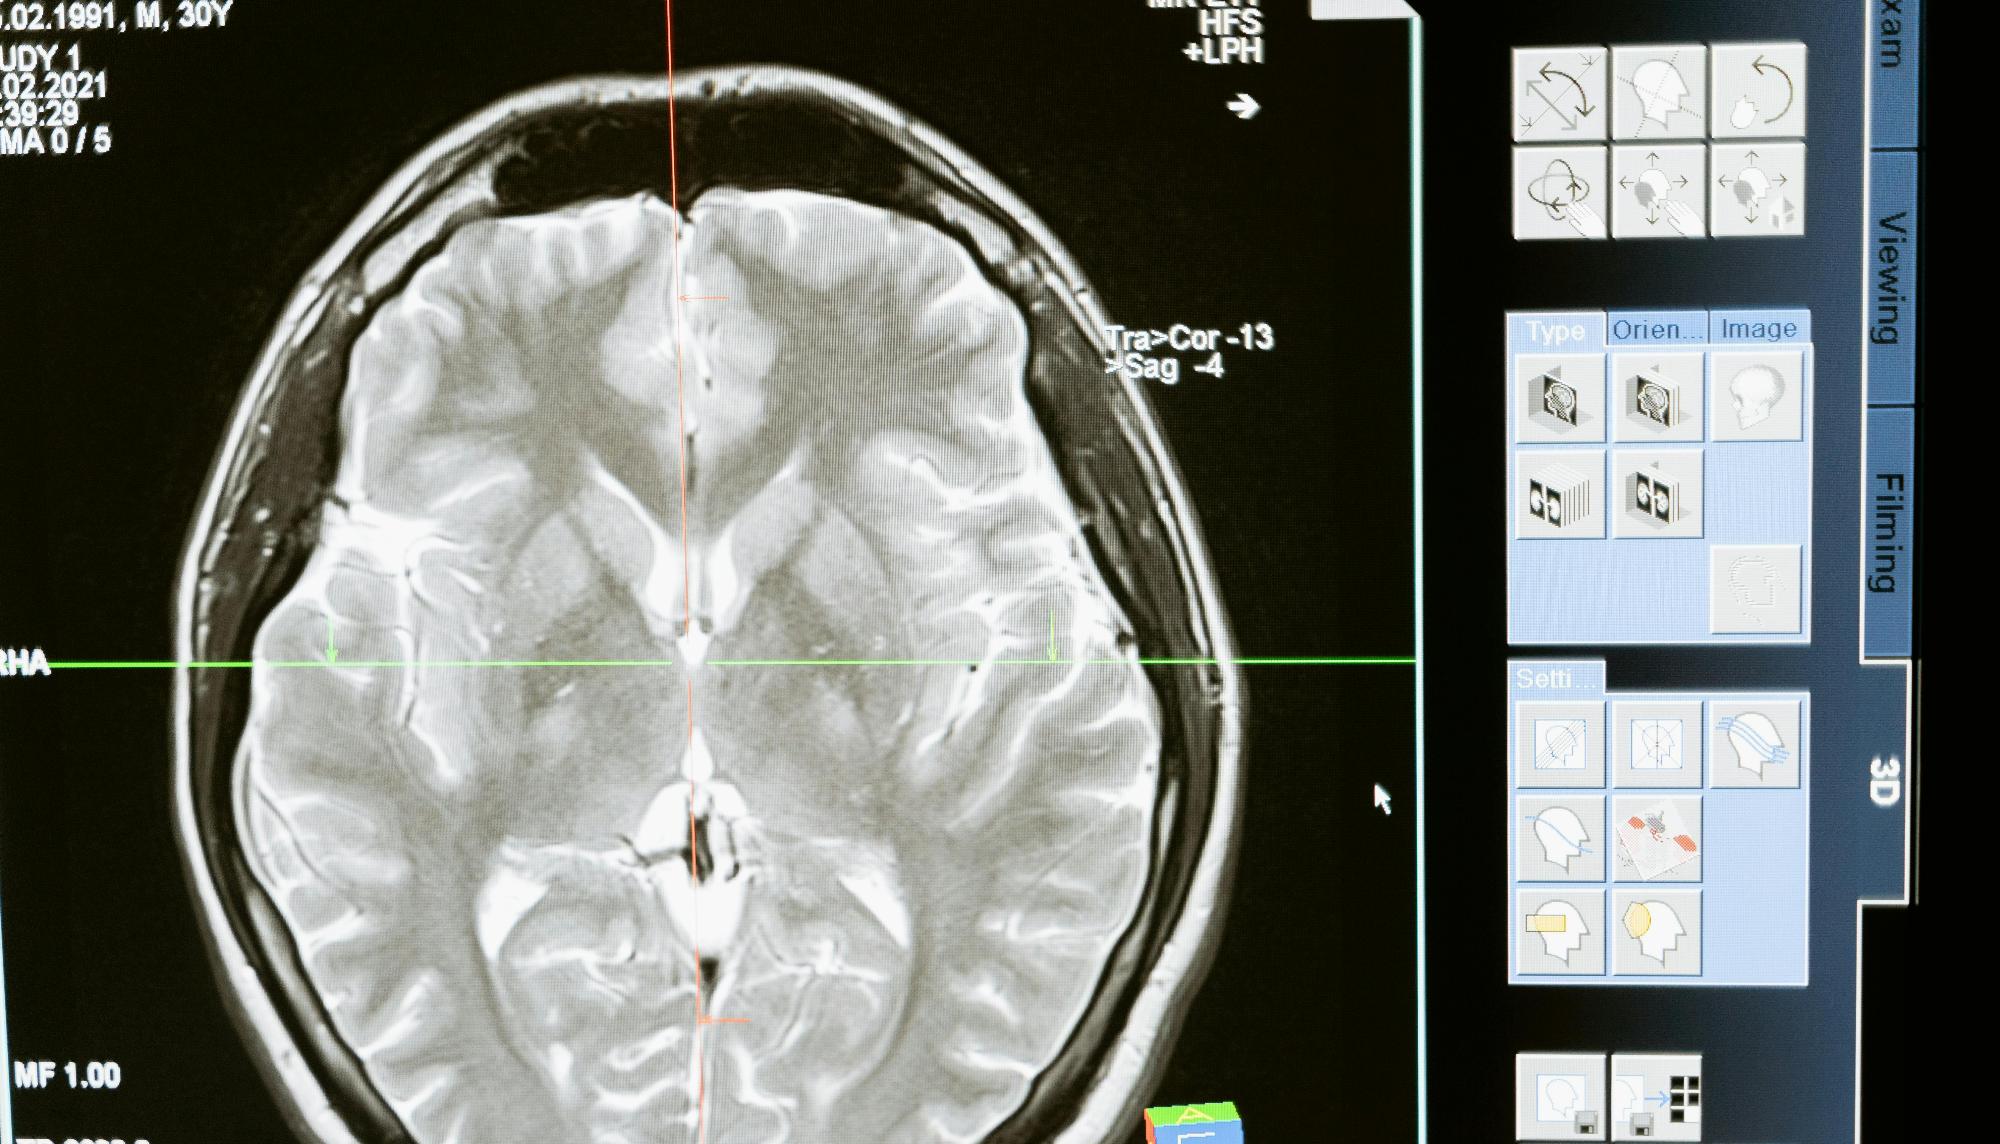

4. КТ, МРТ және ядролық медицина зерттеулерінің нәтижелерін қолданыңыз және түсіндіріңіз, радионуклидтік зерттеулердің тәуекелдерін бағалаңыз. Сканерлеу хаттамалары, контрастты технологиялар, сцинтиграфия. Эндокриндік, жүрек-қан тамырлары, тірек-қимыл аппараты, бауыр және бүйрек патологияларының радионуклидті диагностикасы.